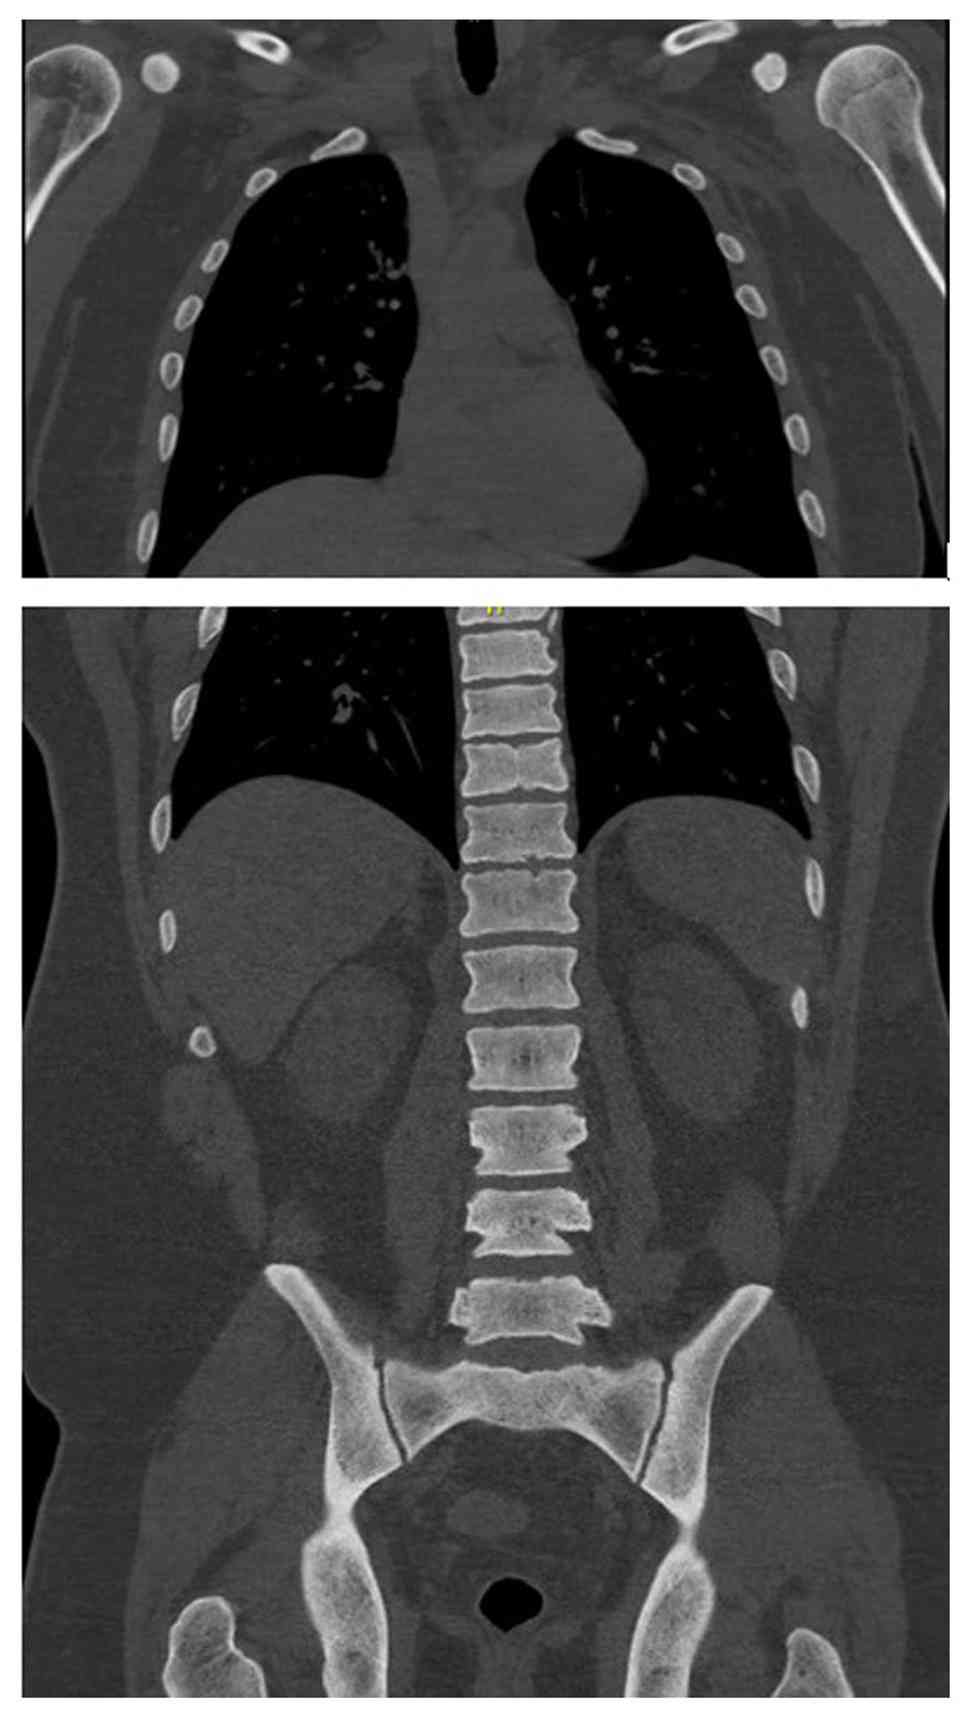

Upon arrival, he was hypotensive and symptomatic. An electrocardiogram (Fig. 1) demonstrated sinus rhythm with peaked T waves. Laboratory results revealed hyperkalemia, elevated levels of troponins (in thousands; ng/l), acute kidney injury and high anion gap metabolic acidosis. Urine drug screening yielded negative results, while salicylate and acetaminophen levels were normal. Other laboratory results are listed in Table I. Imaging analyses, including a computed tomography scan of the cervical spine (Fig. 2), and chest, abdomen and pelvis (Fig. 3), revealed diffuse bony sclerosis.

Computed tomography scan of the chest

(upper panel), and abdomen and pelvis (lower panel) without IV

contrast bone window illustrating the diffuse sclerosis of bony

structures in the humerus head, thoracolumbar vertebrae and pelvic

bones.

Figure 3

Computed tomography scan of the chest (upper panel), and abdomen and pelvis (lower panel) without IV contrast bone window illustrating the diffuse sclerosis of bony structures in the humerus head, thoracolumbar vertebrae and pelvic bones.

Inhalant-related skeletal fluorosis can produce diffuse osteosclerosis, trabecular coarsening, cortical thickening and soft-tissue ossifications, with imaging serving as the most sensitive diagnostic tool. As fluoride accumulates in bone with a long half-life, radiographic changes may persist for years even after exposure stops (15). In the patient in the present study, extensive osteosclerosis was evident despite his young age, consistent with chronic hydrofluorocarbon exposure, although a DEXA scan was not obtained. However, in the present study, serum or urine fluoride levels were not measured to confirm fluorosis; thus, this is a limitation of the present study. Without fluoride quantification, a definitive diagnosis of skeletal fluorosis cannot be made. Instead, toxic-metabolic bone disease from inhalant exposure was considered more likely. The differential diagnosis for diffuse osteosclerosis is limited, but includes osteoblastic metastases (e.g., prostate and breast), sclerotic myeloma, myelofibrosis, mastocytosis, Paget's disease and rare granulomatous disorders, such as sarcoidosis. In the case described herein, malignancy and myeloma were investigated and excluded, and there was no evidence of systemic diseases (such as sarcoidosis) that may cause similar bone changes.